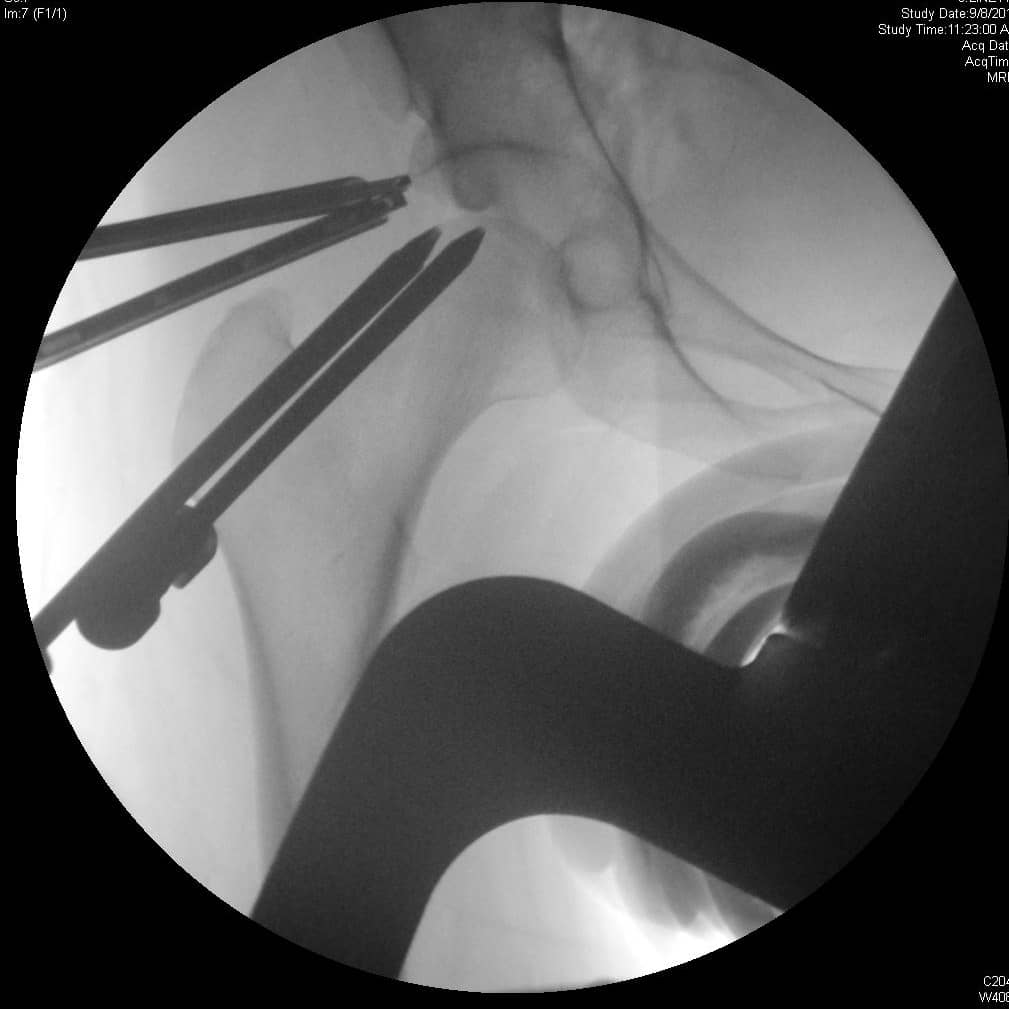

एसिटैबुलर ओस्टियोप्लास्टी और लैब्रल मरम्मत के साथ हिप आर्थ्रोस्कोपी

एफएआई के लिए प्रारंभिक गैर-शल्य चिकित्सा प्रबंधन में गतिविधि संशोधन और विरोधी भड़काऊ दवा शामिल है। शल्य चिकित्सा उपचार की प्रगति उन रोगियों के लिए विचार की जानी चाहिए जो रूढ़िवादी प्रबंधन में विफल होते हैं। ऊरु गर्दन के घावों या लैब्रल आंसुओं के सर्जिकल उपचार का इलाज खुले या आर्थोस्कोपिक डिब्राइडेशन और लैब्रल मरम्मत या शोधन द्वारा किया जा सकता है। खुले उपचार के संकेतों में गैर-गोलाकार ऊरु सिर, सिर-गर्दन ऑफसेट में कमी, पिंसर का टकराव, और पीछे के कूल्हे के घाव शामिल हैं। बर्नीज़ पेरियासेटाबुलर ओस्टियोटॉमी एक खुली एसिटेबुलर रीओरिएंटेशन प्रक्रिया है जिसका लक्ष्य एसिटेबुलर रेट्रोवर्जन को कम करना है। एसिटाबुलम की चोंड्रल चोटों का इलाज चोंड्रोप्लास्टी, ड्रिलिंग या माइक्रोफ्रैक्चर द्वारा किया जा सकता है, जिसका उद्देश्य फाइब्रोकार्टिलेज रीग्रोथ को प्रोत्साहित करना है। एसिटेबुलर एंटीवर्सन और पश्चवर्ती ओस्टियोफाइट के प्रभाव का इलाज एसिटाबुलम के रिम एक्सिशन के साथ किया जा सकता है। आर्थोस्कोपिक नैदानिक परिणाम एफएआई के उपचार के लिए खुले सर्जिकल नैदानिक परिणामों के समान दिखाई देते हैं। 2, 3

एफएआई के लिए सर्जिकल मरम्मत पर्याप्त संयुक्त स्थान वापस करने का प्रयास करती है ताकि एसिटाबुलम के खिलाफ ऊरु सिर या गर्दन के झुकाव के बिना कूल्हे की गति की अनुमति मिल सके। इस स्थान को कम करने वाले घावों का छांटना अपक्षयी प्रक्रिया को संभावित रूप से धीमा करने और दर्द और अन्य लक्षणों को हल करने के लिए किया जाता है। आर्थ्रोस्कोपी समान नैदानिक परिणामों के साथ पारंपरिक खुली सर्जरी के लिए एक कम-आक्रामक विकल्प प्रदान करता है। 4, 7

लैब्रल मरम्मत और एसिटेबुलर ओस्टियोप्लास्टी के साथ हिप आर्थ्रोस्कोपी के बाद रोगी संक्रमण, तंत्रिका चोट, या संयुक्त अस्थिरता के संकेतों के बिना क्लिनिक में लौट आया। वह छह सप्ताह के बाद तक बैसाखी पर गैर-भार वहन करेगी, जिस समय उसे सहन करने के रूप में वजन वहन करने के लिए उन्नत किया जाएगा।